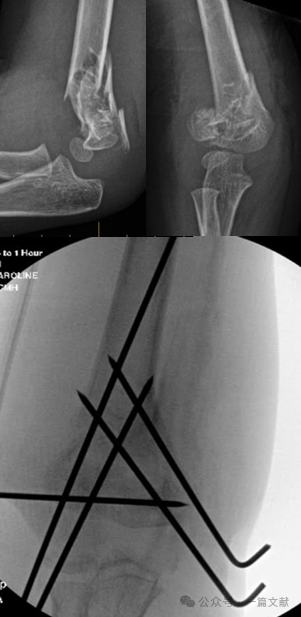

IV. Non-Operative Treatment: Avoid casting the swollen elbow in greater than 90 degrees of flexion. Close follow-up is essential, especially for Type 2 fractures. If treated with closed reduction alone, the loss of reduction rate can be as high as 48% within the first week. Risk factors for displacement include: greater initial displacement, Type 2B fractures, and patients with larger upper arm circumference. As shown in the figure, a patient treated conservatively had fracture displacement on follow-up X-ray at 3 weeks and subsequently underwent surgical fixation with K-wires.

* Ideal Pin Placement Requirements: Use 1.5-2 mm K-wires. Pins should engage the medial and lateral columns with a divergent pattern. Greater separation between pins increases stability. As shown in the figure, pin configurations for Type 2A, 2B, and 3 fractures.